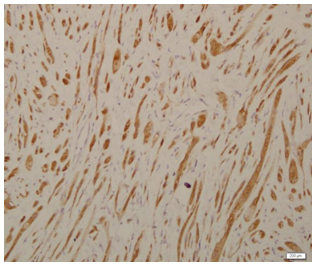

An excision biopsy specimen from a mass at elbow of 26 years old female patient was received for histopathological examination. The clinical impression was of ‘benign soft tissue tumor’. The specimen was received in 10% formalin in one container. On gross examination, it was a 1.5 x 1 x 0.5 cm well-circumscribed, grey-tan mass, without skin component. The cut surface was solid homogenous and no necrotic or hemorrhagic areas were found on it. The microscopic examination revealed a circumscribed encapsulated lesion composed of round to polygonal to spindle shaped cells with eosinophilic granular cytoplasm and centrally placed small nuclei (Figure 1 & Figure 2). Cells were arranged in intersecting bundles and mixed with fibrous connective tissue (Figure 3). The Intralesional peripheral nerve bundles surrounded by the lesional cells were seen (Figure 4). No significant mitoses or cells with cross striation, significant inflammatory infiltrate or necrosis were seen. IHC showed positive results for S100 (Figure 5) and neuron-specific Enolase (NSE) (Figure 6). Smooth muscle actin (SMA) (Figure 7) and Myogenin were negative. CEA was focally positive. Periodic acid-schiff (PAS) stain showed PAS positive intracytoplasmic granules (Figure 8). The lesion was completely excised with <1mm safety margin. Focal entrapment of the adjacent fatty tissue was observed. Based on the above mentioned findings, diagnosis of granular cell tumor (GCT) was made.

Figure 5 S100.